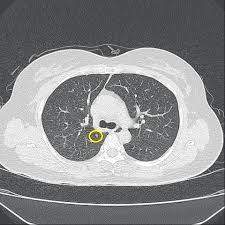

폐결절(pulmonary nodule)은 폐 안에 지름 3cm 이하의 작은 덩어리나 불투명 부위로, 흉부 X‑선이나 CT 검사에서 우연히 발견되는 경우가 많습니다. 대부분은 무증상이며, 양성인 경우가 많지만 일부는 악성(암)일 수 있어 주기적인 관찰이 필요합니다.

- 흉부 X‑선 또는 흉부 CT로 발견

- 결절 크기·형태·경계·석회화 여부 등 특징 분석